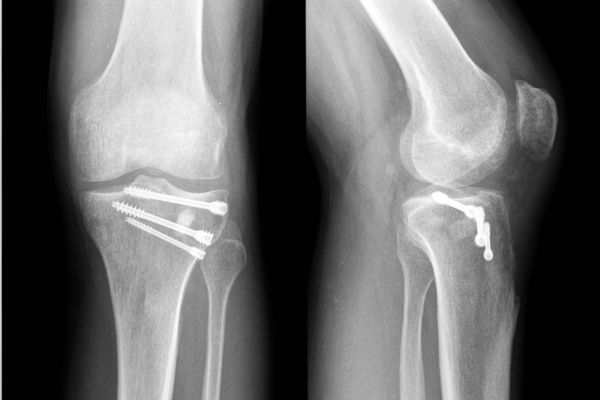

Gabinet ortopedyczny prowadzony przeze mnie specjalizuje się w leczeniu schorzeń i urazów kończyn górnych i dolnych. Zajmuję się leczeniem choroby zwyrodnieniowej stawu biodrowego i kolanowego, uszkodzeń wewnętrznych stawu kolanowego i barkowego, złamań w obrębie kończyn górnych i dolnych oraz urazów ścięgien i mięśni kończyn górnych i dolnych. Ponadto wykonuję diagnostykę USG narządu ruchu i badanie preluksacyjne (USG bioderek niemowląt). Leczę również neuropatie uciskowe kończyn (zespół kanału nadgarstka, rowka nerwu łokciowego, kanału Guyona) oraz uszkodzenia wewnętrzne stawów kończyn górnych i dolnych. Zapraszam do mojego gabinetu, gdzie dobiorę odpowiednie do schorzenia metody leczenia i zakwalifikuję do ewentualnego leczenia operacyjnego. W celu umówienia się na wizytę proszę o kontakt telefoniczny z rejestracją gabinetu ortopedycznego w Lesznie.